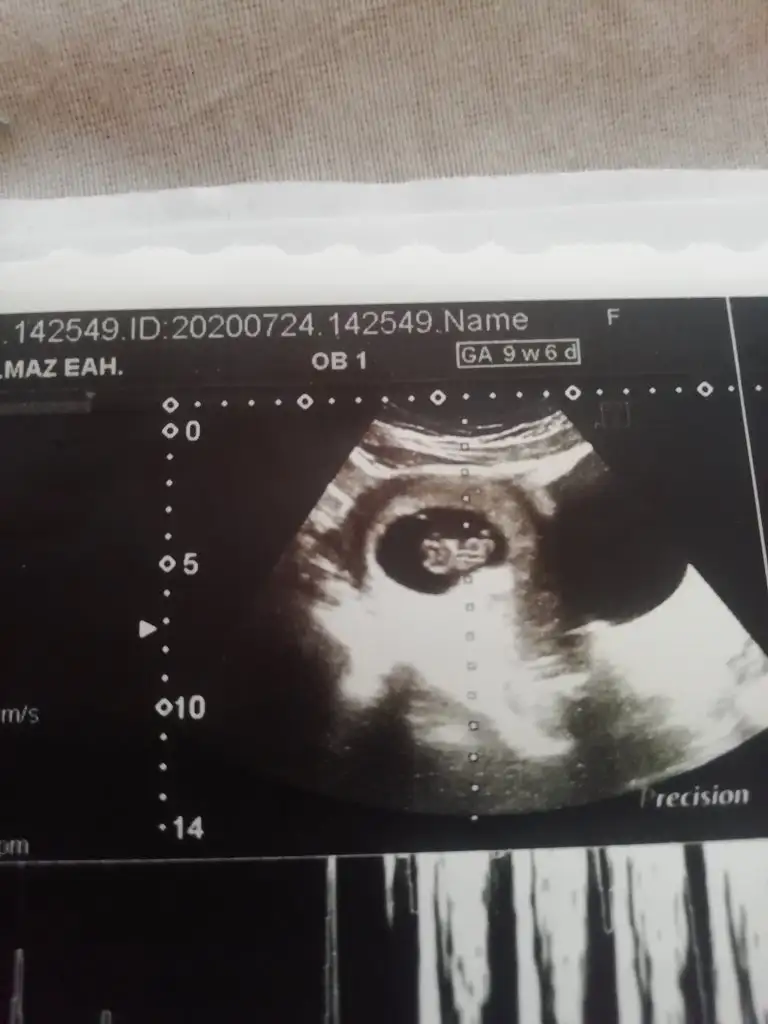

Erkek gibiMerhaba herkese Ikra meyra bebegimin ultrosan fototsunu attim banada yorum yapabilir misin lutfen 11+3

İkra meyra benim bebeğimin cinsiyetine de yorum yapabilir misin

Net değil olursa 12-13 hafta tekrar paylaşınSelam arkadaşlar, biz de bugün 11+4 olduk. Cinsiyet tahmini alabilir miyiz ☺